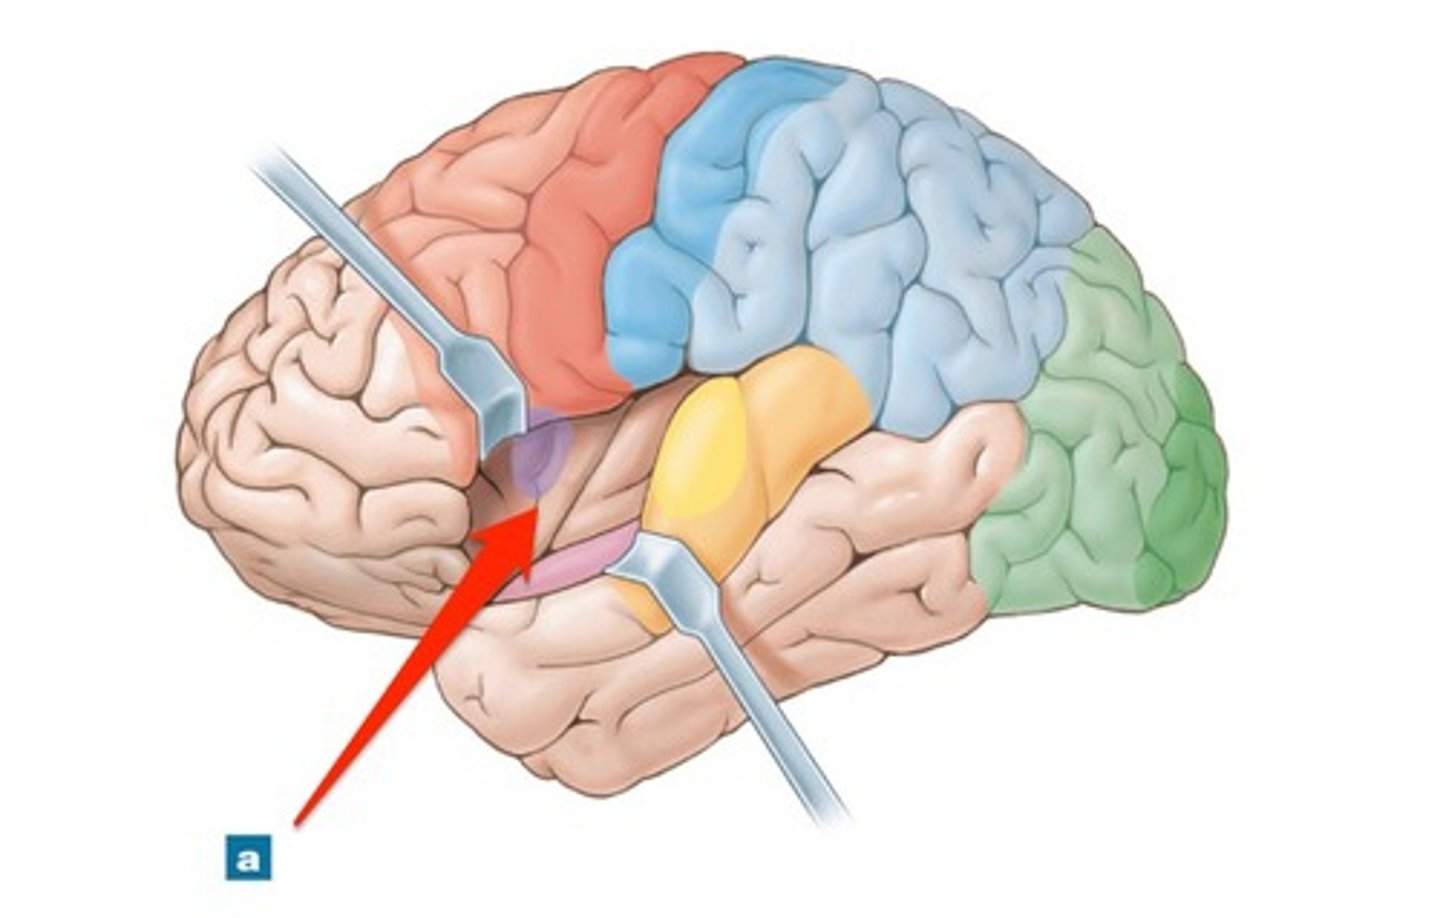

lobes of the cerebrum

frontal, parietal, temporal, occipital, insula

frontal lobe

Regions of the cerebrum involved in:

•Voluntary motor functions

•Motor control, concentration, verbal communication, decision making, planning, personality

parietal lobe

Region of the cerebrum that:

•receives and integrates general sensory information (shape, texture), taste and some visual processing

occipital lobe

•primary visual center of brain (vision and visual memories)

temporal lobe

Regions of the cerebrum that:

•contains areas for hearing, smell, learning, memory, and some aspects of vision and emotion

central sulcus

separates frontal and parietal lobes

lateral sulcus

Separates temporal lobe from parietal and frontal lobes